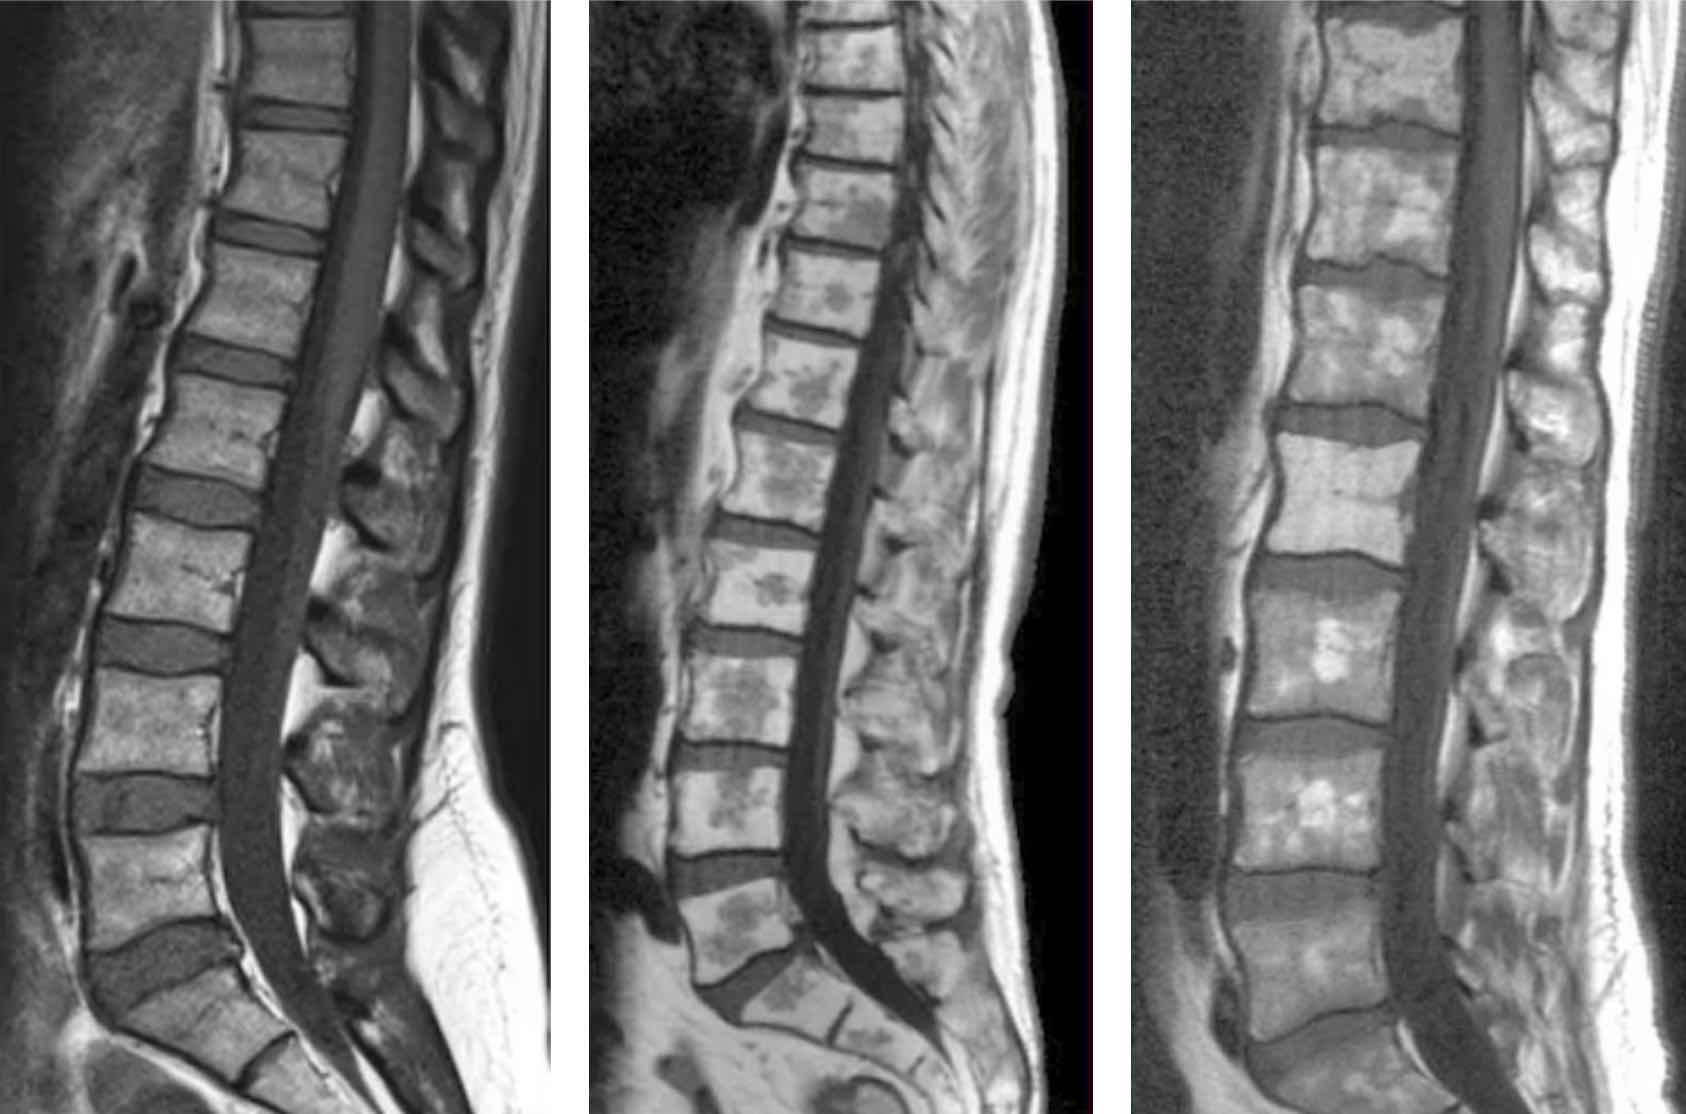

Séquences sagittale T1, sagittale et coronale T2 STIR, ainsi que 3D T2.

aspect normal moelle jaune (graisse) = HT1 avec ilôts de moelle rouge (hématopoïétique) = hT1

aspect normal moelle jaune (graisse) = HT1 avec ilôts de moelle rouge (hématopoïétique) = hT1

apparition progressive moelle jaune dans les membres = épiphyses > diaphyses > métaphyses

apparition progressive moelle jaune dans les membres = épiphyses > diaphyses > métaphyses

Modifications

- ↗ moelle jaune = fracture ancienne, discopathie Modic 3, radiothérapie

- ↗ moelle rouge (épargne les apophyses et épiphyses) = sportif, fumeur, obèse, anémie, G-CSF

reconversion médullaire = ilôts hT1 avec faible rehaussement

reconversion médullaire = ilôts hT1 avec faible rehaussement

moelle en hT1 par rapport au disque et HSTIR par rapport aux muscles

moelle en hT1 par rapport au disque et HSTIR par rapport aux muscles

=> à confronter au bilan biologique avec électrophorèse des protéines sériques